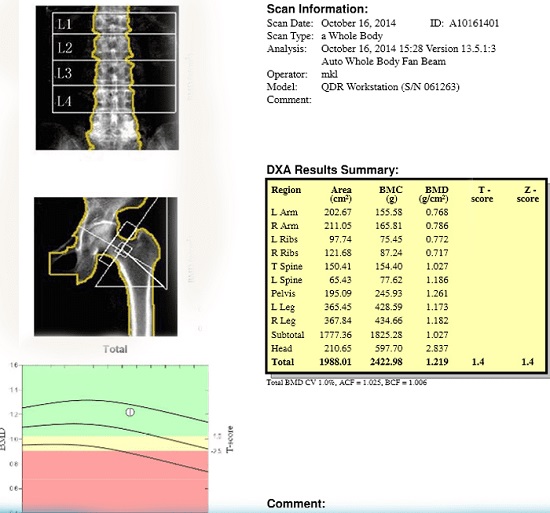

به گزارش روابط عمومی دانشگاه علوم پزشکی شهید بهشتی، سنجش تراکم استخوان (Bone Mineral Densitometry) یا BMD، روشی برای تعیین میزان مواد معدنی موجود در هر سانتیمتر مکعب استخوانهای بدن و در اصل نوعی شاخص مهم در شناسایی پوکی استخوان و احتمال شکستگی استخوانها است. تست تراکم استخوان اغلب از دو استخوان لگن و ستون فقرات انجام میشود.

شناسایی درصد تراکم استخوان با تفسیر آزمایش تراکم استخوان انجام میشود. در این آزمایش ۲ پارامتر وجود دارد که با T و Z نشان داده میشود. عدد T به مقداری اشاره دارد که فرد آزمایش دهنده، در حالت سالم و نرمال باید داشته باشد. عدد Z نیز در مقایسه با دیگر افراد همسن، نژاد و جنسیت مقایسه میکند.

محدوده مجاز و نرمال این اعداد در زیر آمده است:

• محدود طبیعی و سالم عدد T، بین ۱ و منفی ۱ است.

• اگر عدد T بین منفی ۱ و منفی ۲/۵ باشد، احتمال پوکی استخوان در آینده وجود دارد.

• اگر عدد T منفی ۲/۵ یا کمتر باشد، فرد به پوکی استخوان مبتلا است.

• محدوده طبیعی عدد Z هم بالاتر از عدد منفی ۲/۵ است.